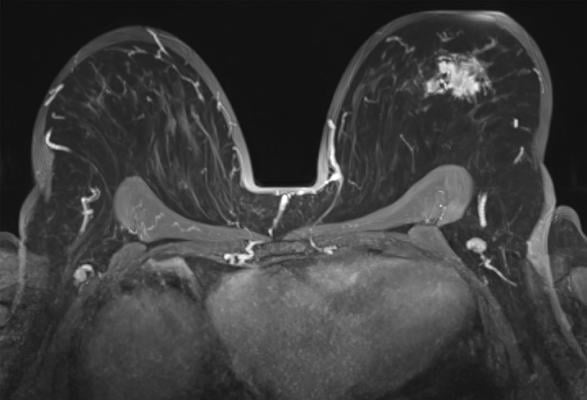

Breast MRI with a tumoral lession in the left breast, axial view. Getty Images

Breast MRI has become the preferred method for imaging women with personal history of breast cancer. Previous studies have shown that breast MRI has a higher cancer detection rate than mammography.

Dr. Lee and colleagues studied the link between second cancer risk and background parenchymal enhancement (BPE) at surveillance breast MRI. BPE refers to the brightening, or enhancement, of background tissue on MRI after administration of a contrast agent. The degree of BPE can vary between and within women. It is thought to be related to changes in the blood supply and permeability of breast tissue, which is affected by hormonal status. Breast cancer treatment in the form of radiation therapy, chemotherapy or endocrine therapy can also alter the BPE in the treated breast.

BPE on contrast-enhanced breast MRI is a known risk factor for breast cancer. Less is known about the links between BPE at surveillance breast MRI and the risk of second breast cancer.